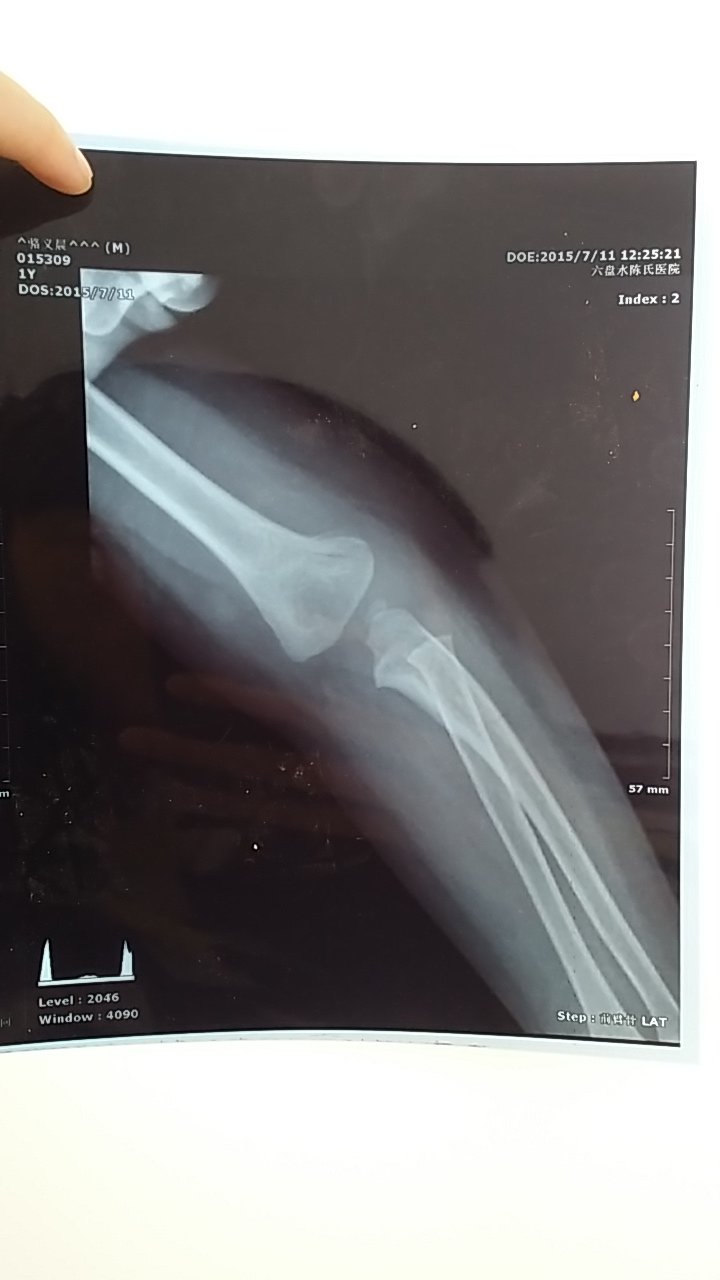

宝宝一岁半 男宝宝 今天从茶几摔下来 拍片了 医生说骨折了 打了石膏 说一两个星期去复查 请 宝宝一岁半 男宝宝 今天从茶几摔下来 拍片了 医生说骨折了 打了石膏 说一两个星期去复查 请问这骨折严重吗? 点击展开 匿名用户 2015-07-11 17:20 满意回答 不严重,就是线性骨折。带娃编殖娃小心卜震点,小潜葛辨朋友受伤严重会影响以后发育的。 匿名用户 2015-07-11 17:50 宝宝知道提示您:回答为网友贡献,仅供参考。 为您推荐: 其他回答 额 匿名用户 2015-07-11 17:28 严重骨头都分开了 匿名用户 2015-07-11 17:21 相关问题 小孩八岁脚踝骨折打了石膏,说一星期复查,不知道复查需要拆了石膏再拍片吗? 专家你好!我想问;小孩骨折五个星期,石膏拆了,手还是伸不直,应该怎么办 您好,女儿右胳膊肘摔骨折了,但没移位,打了石膏